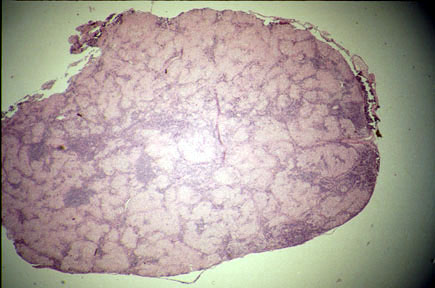

Nodes